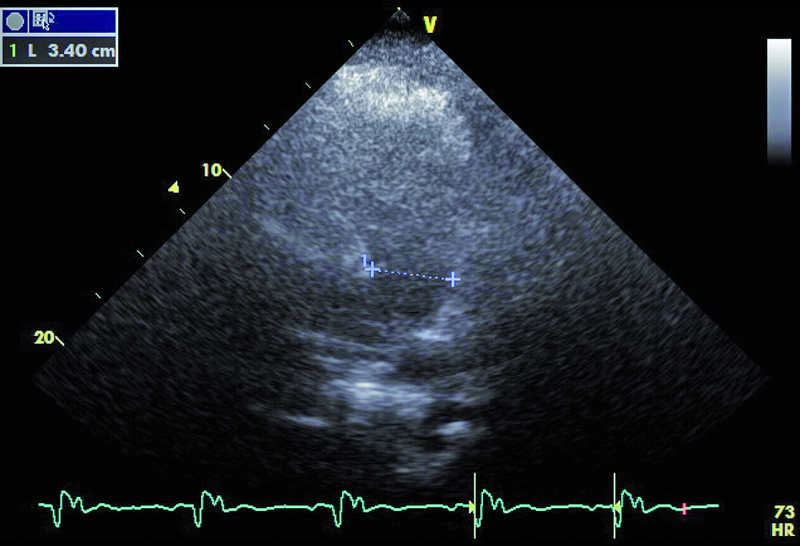

Mężczyzna, lat 30. Jakie patologie można rozpoznać na rycinach?

1. Poszerzenie opuszki aorty (ryc. 1, 2).

2. Powiększenie jamy lewego przedsionka (ryc. 1).

9. Komorowe zaburzenia rytmu (ryc. 1, 6).